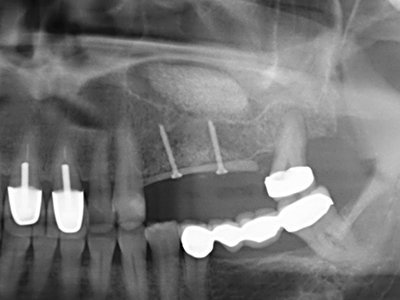

Fig. 1: Preparation of a bone cover with the Piezomed (W&H Salzburg, Austria).

Fig. 2: Vertical and horizontal lateral maxillary defect with a high smile line with indication for pre-implant reconstruction.

Fig. 11: The postoperative panoramic image shows the vertical augmentation and sinus floor elevation.

Fig. 12: After six months of healing, the alveolar ridge is vital and sufficiently dimensioned in all planes.